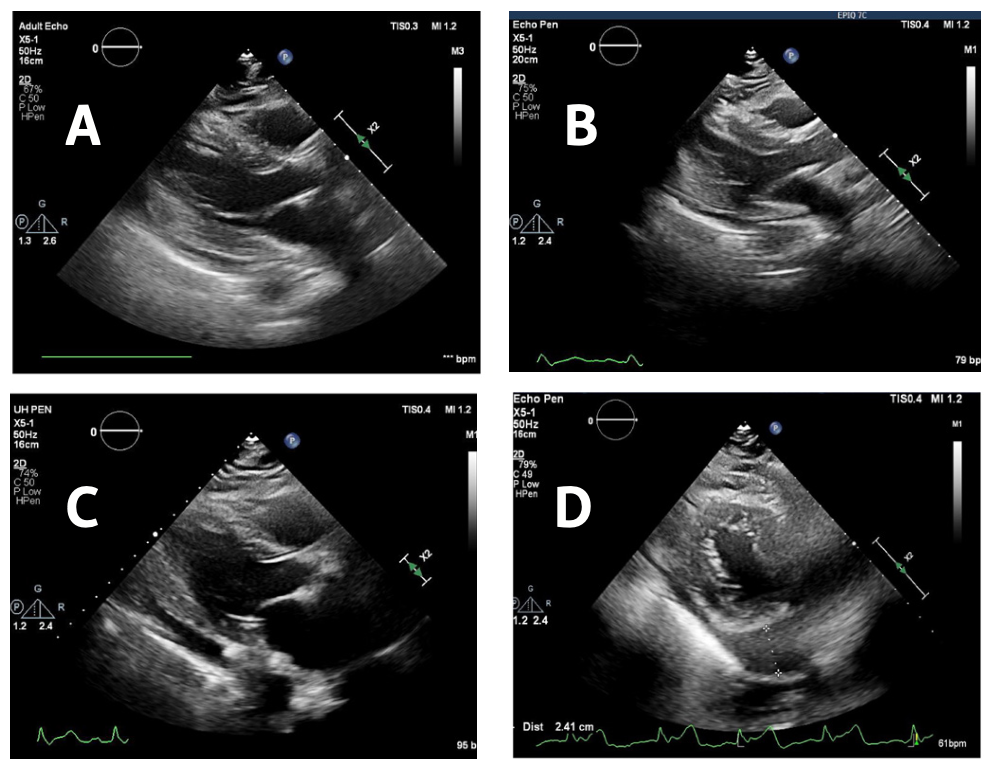

Among patients who received the Watchman Legacy device, 2 patients developed AE and none developed DE. One of the effusions happened intraoperatively due to cardiac perforation and required surgical repair. Of those receiving the Watchman FLX device, 1 patient developed AE and 2 patients developed DE. One patient presented 24 hours after the procedure with chest tightness and was found to have an increase in effusion size compared with preprocedure echocardiogram. The effusion gradually increased over the ensuing 48 hours and she underwent a pericardial window due to the posterior location (Figure 1). The second patient complained of lightheadedness 8 hours after the procedure and was found to be hypotensive, requiring urgent pericardial drainage. The remaining patients were also successfully treated by pericardiocentesis. All 5 patients with effusion underwent imaging with CT scan or TEE 45 days after their procedure and did not have a significant peridevice leak, thrombus, or device embolization. None were readmitted after pericardial intervention. One patient with DE had persisting small anterior pericardial effusion on follow-up CT scan. The remaining 4 patients had trivial or no effusion on follow-up imaging.